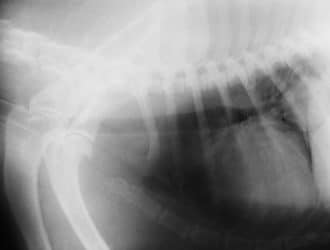

Dog health issues

With regards to dog illnesses, there are lots of potential ailments that can catch you…